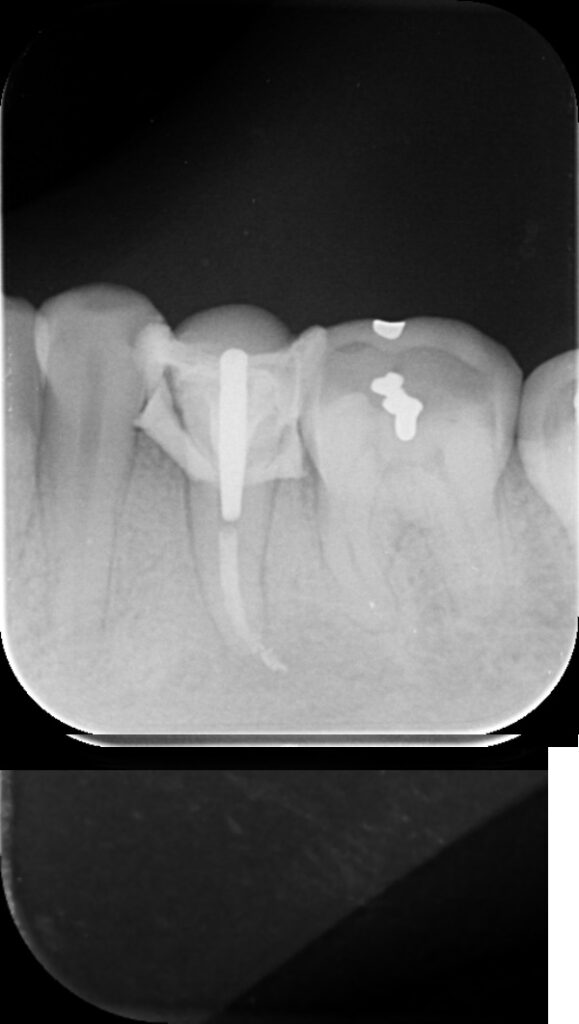

Final J0

Radio à 1 an = C’est gagné ! ( pour l’instant! )